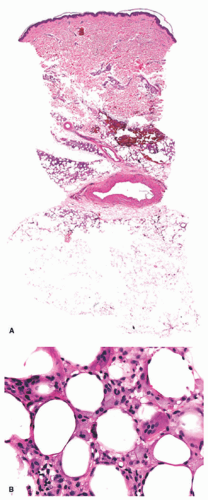

In early lesions, this disorder presents with lipophagic panniculitis, characterized by a dense mixed inflammatory infiltrate centered on the subcutaneous fat lobules, with numerous foamy lipophages (Figure 5-7A and B).22 Neutrophils are often present in early disease, with histiocytes predominating in later lesions. There is no vasculitis. In very established lesions where clinical atrophy is longstanding, the infiltrate may be sparse, with notable atrophy and fibrosis of the fat lobules.20

![]() FIGURE 5-7. Lipoatrophic panniculitis histopathology: lobular panniculitis with fat necrosis (A). High-power view highlighting lipophagic fat necrosis and foamy histiocytes (B). |